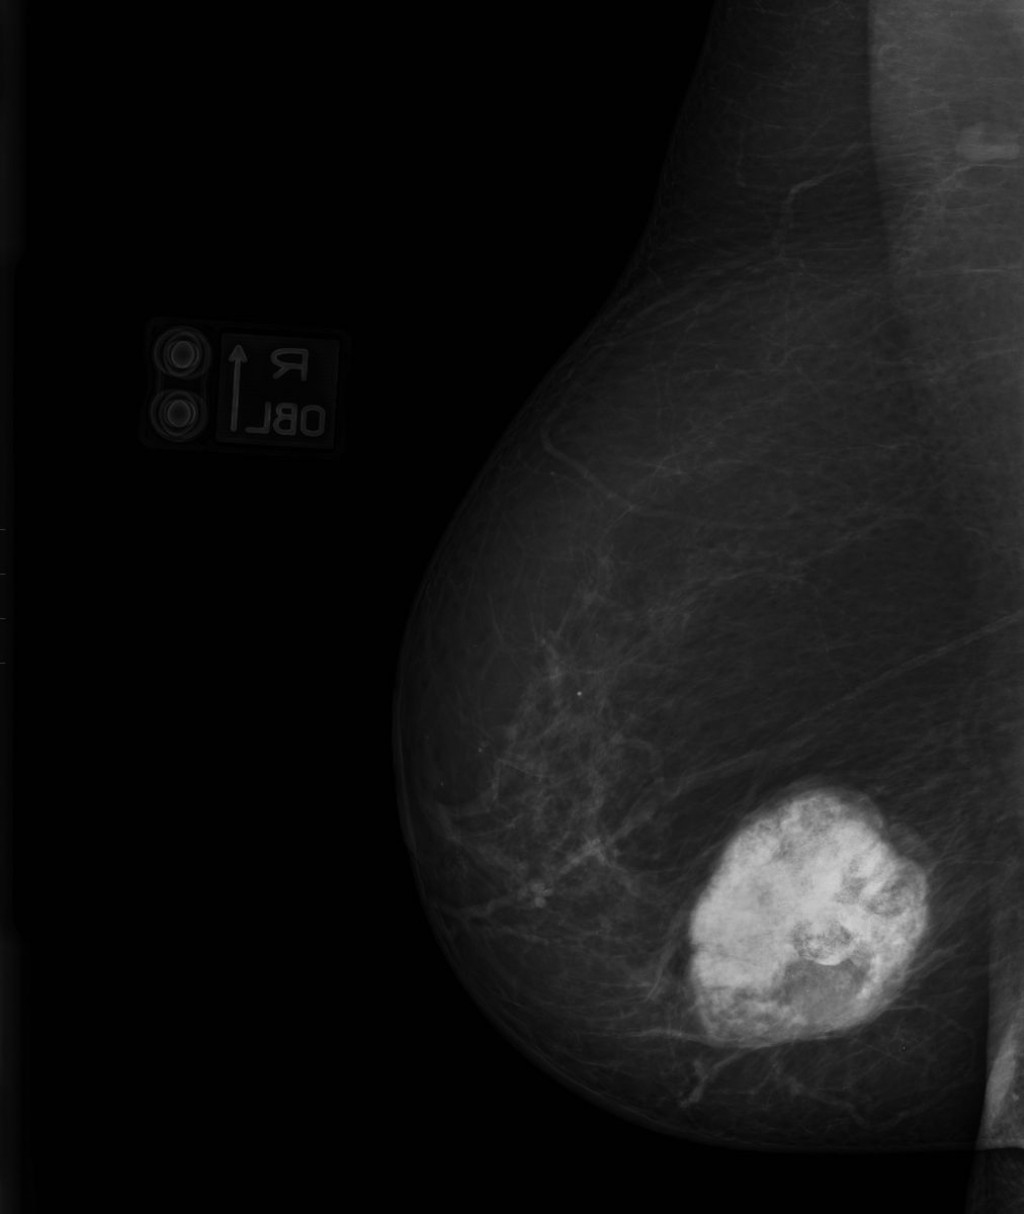

Фиброаденома молочной железы - доброкачественное образование, которое часто встречается у женщин. Оно может быть обнаружено при помощи различных методов диагностики, включая маммографию. Ниже представлены фотографии, помогающие понять, как выглядит данное заболевание.

Опухоль на снимке маммографии

Злокачественные опухоли молочных желез

Маммография и ее роль в диагностике фиброаденомы молочной железы

Маммография - это рентгенологическое исследование молочных желез. Оно позволяет выявить различные изменения в тканях, включая фиброаденому. На маммограммах можно увидеть структурные особенности опухоли и отследить ее динамику во времени.